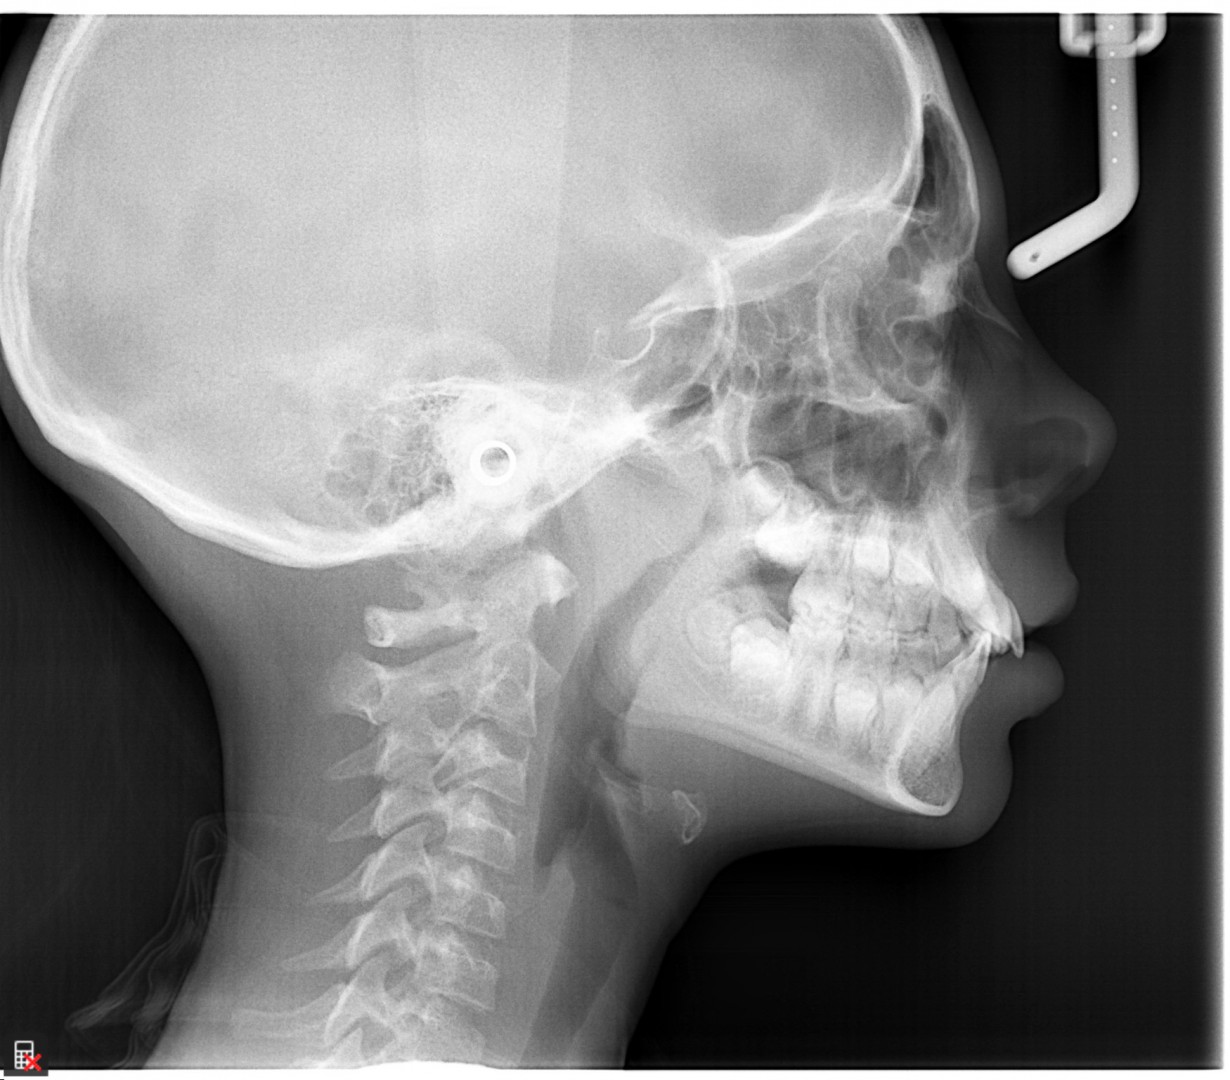

This is a 9yo girl with a high esthetic desire (wants to be a model/actor). She avulsed tooth #9 about 3 years ago, and she has been under treatment with other endodontists. I guess they attempted revascularization with MTA about year ago. #9 is ankylotic with a few mm’s infraposition. It is gray due to the MTA. #8 is slightly yellow/white due to calcification/obliteration but she says she feels cold testing and it is otherwise asymptomatic.

I spoke to her about the following options for #9:

1) Decoronation and a fake tooth for her teenage years

2) No treatment, except internal bleach then bonding/veneer.

3) Autotransplantation of a mandibular premolar

4) Segmental osteotomy/corticotomy later

Are they any other options available? How would you approach this case? Thanks in advance!